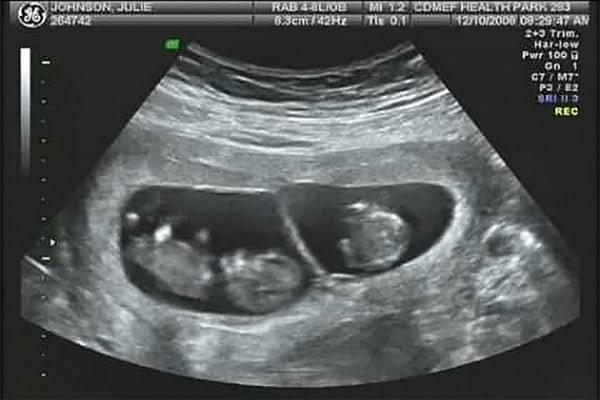

По УЗИ определить однояйцевую беременность наверняка можно только в том случае, если между плодами отсутствует перегородка.

Наверняка определить количество плодов можно только по УЗИ. Исследование покажет также предлежание, размещение, тип и количество плацент и плодных мешков, объем амниотической жидкости, физическое состояние плодов и состояние кровотока в матке.

Из-за повышенной вероятности патологий УЗИ при многоплодной беременности делают чаще, чем при вынашивании одного ребенка. При монозиготной – каждые две недели, при двуяйцевой – 1 раз в месяц.